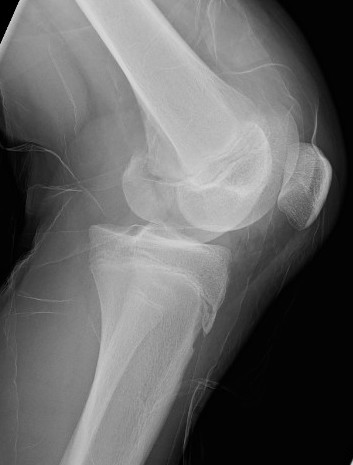

Salter Harris Type II with large Thurston Holland fragement

Distal Femur SH2 ORIFDistal Femur SH2 ORIFDistal Femur SH2 Lateral